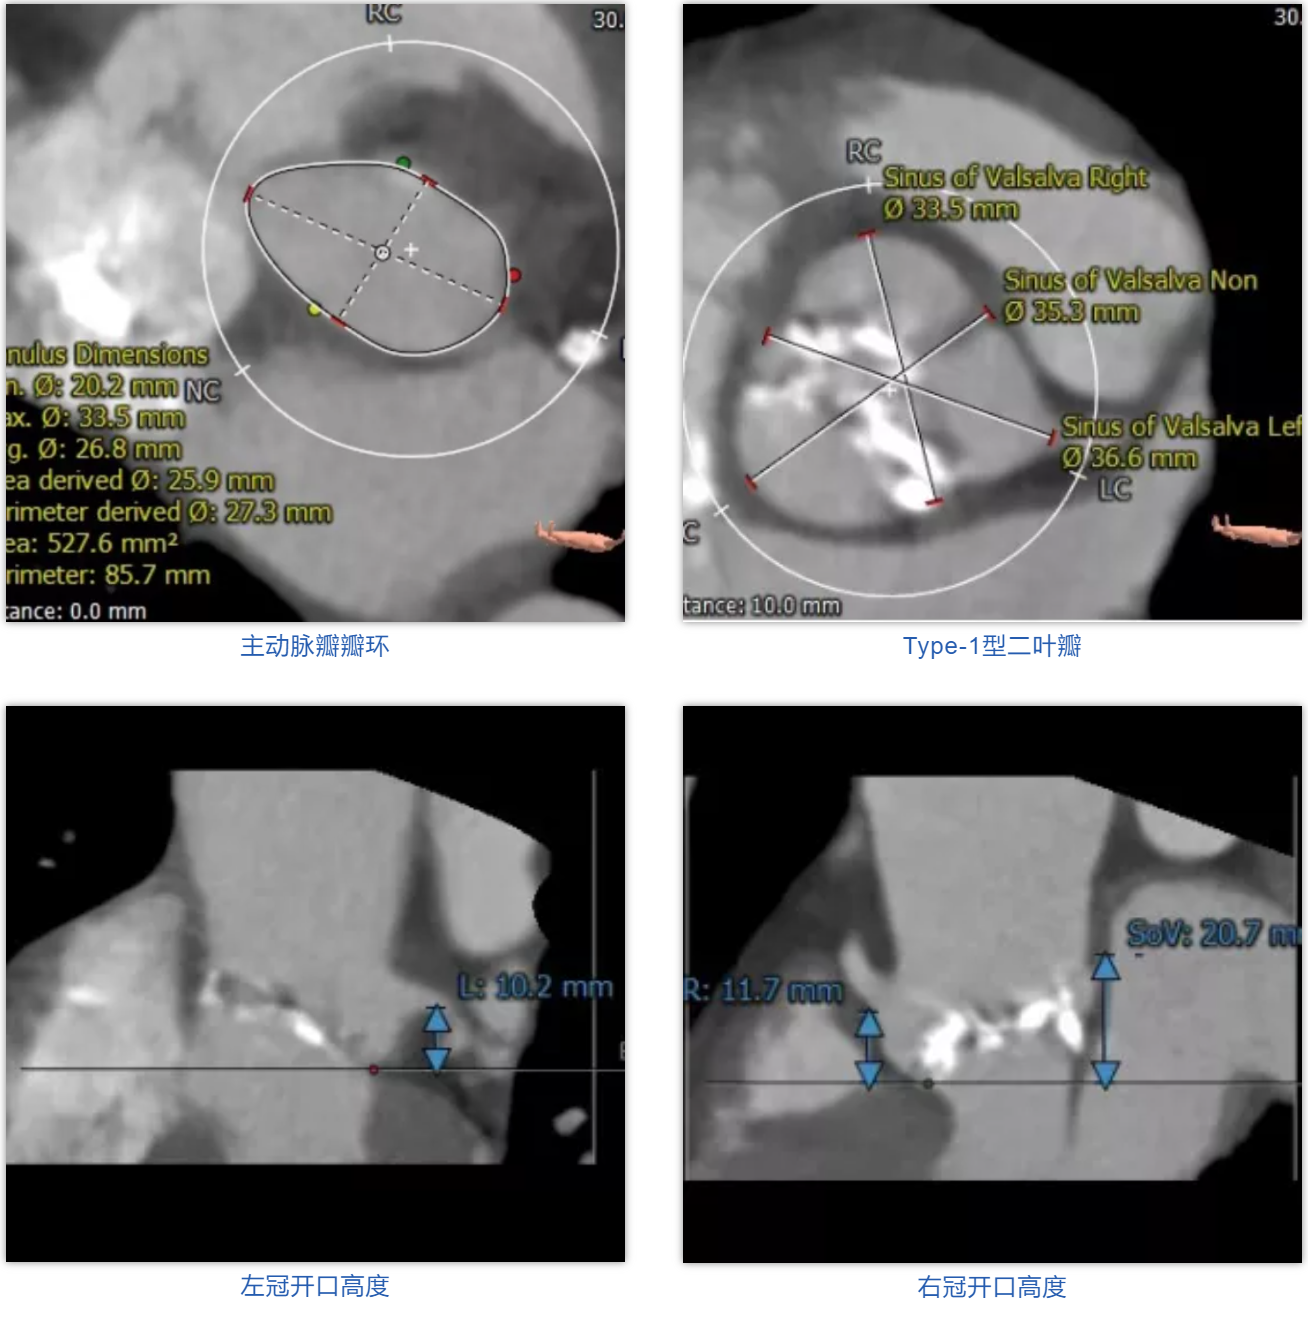

患者男性,67岁,因“劳累后胸闷4月余”入院,术前心脏超声提示主动脉瓣钙化,重度狭窄并轻-中度反流。患者STS评分11.0%,属于常规外科换瓣手术高风险。CT评估结果显示主动脉瓣为Type-1型二叶瓣,瓣叶增厚钙化,瓣环平均直径26.8mm,瓣环面积527.6mm²,面积径25.9mm。左冠脉开口高度10.2mm,右冠脉开口高度11.7mm。术前经详尽影像学重建、评估及病例讨论,测量瓣环直径、分析二叶瓣结构,评估冠脉梗阻风险后,计划植入25# Renatus介入主动脉瓣。

外周血管评估